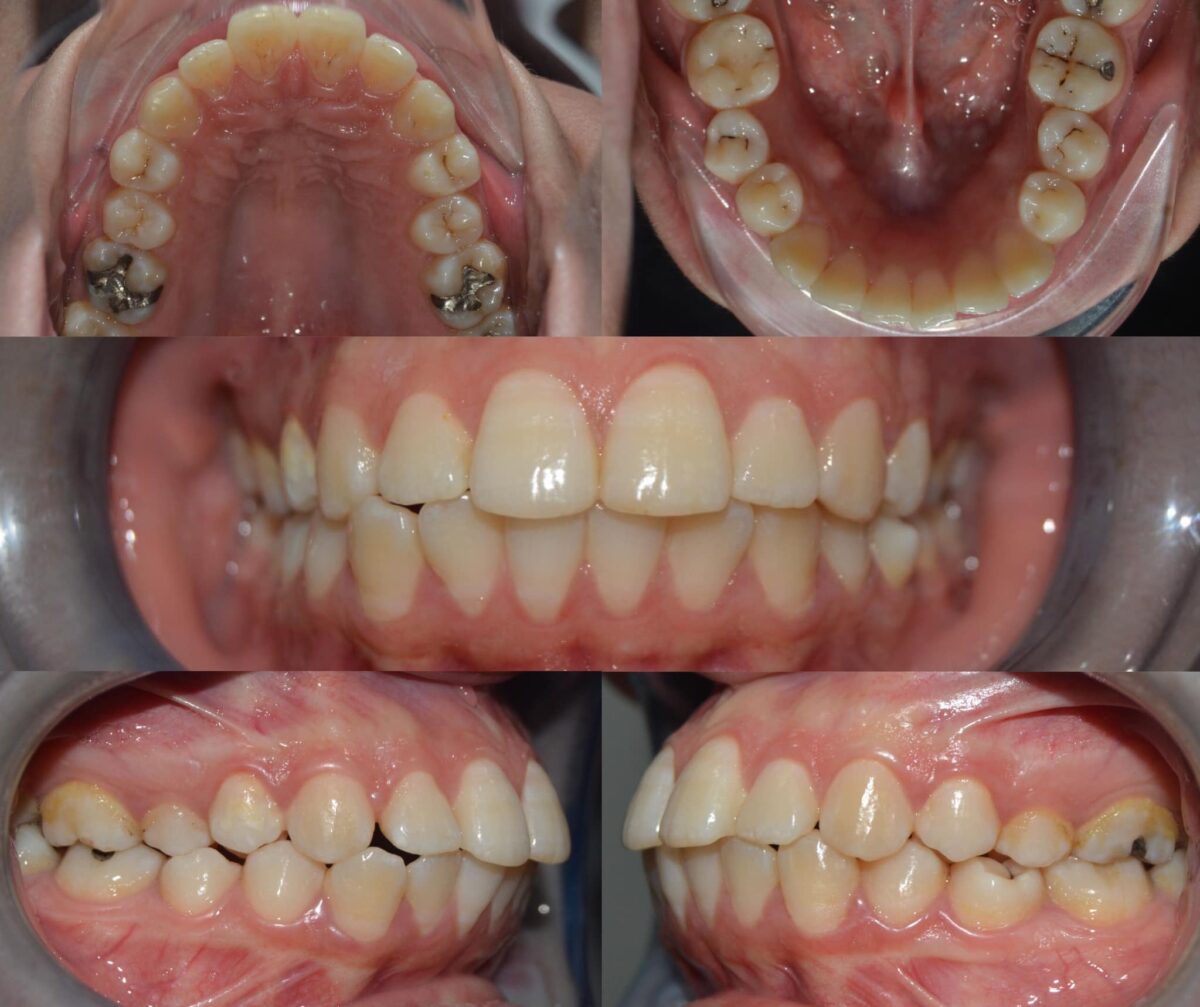

للي محتاجين تقويم، سواء معدني أو شفاف، العيادة بتوفر أحدث حلول التقويم المناسبة لكل حالة، مع متابعة دورية لضمان تقدم العلاج بالشكل المطلوب. وكمان لو في فقدان سن، بيتم تعويضه بزرعات أسنان من التيتانيوم المعتمد دوليًا بعد فحص شامل لعظام الفك وأشعة دقيقة، لضمان أفضل ثبات ونتيجة تدوم سنين.